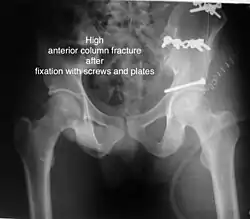

High anterior column fracture after fixation with screws and plates

High anterior column fracture 3 D CT scan picture -

| Anterior column | This fracture is uncommon, typically occurring when the injuring force is applied from the side, against the greater trochanter of the femur bone, as in a fall on the side or being hit on the side. Depending on the location, the fractures are described as very low, low, intermediate and high anterior column fracture. | Anterior column + posterior hemi transverse | In this variety of fractures, the posterior or ilio ischial column is broken as a transverse fracture, while the anterior or ilio pubic column is broken into multiple pieces. Part of the weight-bearing dome in this variety of fractures is still attached to that part of the iliac wing, which forms part of the iliac joint. This type of injury has to be differentiated from both column fractures, where the weight-bearing dome is a floating piece not attached directly to the bone-forming sacroiliac joint.

Typically, it is caused by a combination of forces acting on the hip through the femoral head. All three X-ray views plus a CT scan are a must for the diagnosis and management of this complex injury. In this injury, non-operative treatment rarely gives satisfactory results. Surgical management is ideal. The choice of approach rests with the surgeon but going from the front or anterior approach is necessary. The posterior injury may be tacked with the anterior approach by an experienced surgeon. If the patient is unfit to undergo major surgery due to any reason, longitudinal traction to achieve secondary congruence of the hip may help to restore hip function, though partially. |